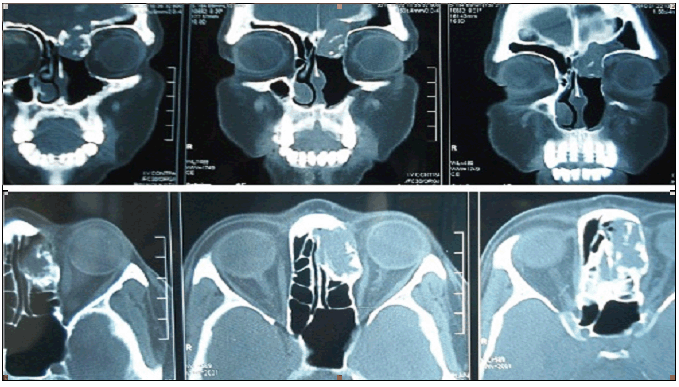

One 55-year-old, hypertensive female patient was admitted in the emergency department with history of intermittent nasal bleeding and headache of one week duration. She was being treated for chronic sinusitis for last eight months. She had undergone left rhinotomy with removal of frontonasal polyp and then removal of ethmoidal polyp after three months interval. The biopsies were diagnostic of inflammatory non-malignant lesions. With onset of new symptoms of nasal bleeding, endoscopy examination was repeated to show recurrence of polyp. Computed tomography scan of the face showed a mass in left anterior ethmoid sinus with extension into the floor of anterior cranial fossa. Medially the lesion eroded the lamina papyracea with no obvious intraorbital extension. Localised bone erosion was noted (Figure 1). Left ethmoid sinus was explored and mass was excised. The biopsy report was suggestive of epithelial cell aggregates with densely cellular fascicles of spindle cells surrounding the epithelial cells, suggestive of biphasic synovial cell sarcoma (Figure 2A, B). Diagnosis was confirmed with immunohistochemical positivity for EMA (focal), Mic-2, bcl-2, calponin, S-100 and CD-56 (focal) but negative for CD-34 and cytokeratin. CT Scan of thorax and ultrasonography of abdomen were negative for metastatic disease. Postoperatively she received only radiation, 50 Gray (Gy) in five weeks, in 25 fractions (200 centiGy dose per fraction). One year into follow up there is no evidence of recurrence of disease.

Figure 1: CT scan of ethmoid sinus mass with extension into the floor of anterior cranial fossa and medially eroding the lamina papyracea with no intraorbital extension.